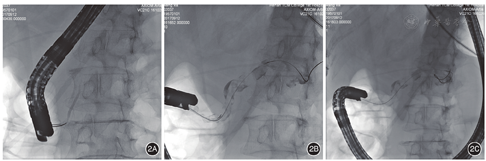

患者女,60岁,因"间断腹痛、腹胀5年余,加重10 d"收入院。患者5年前无明显诱因突发腹痛、腹胀,伴恶心、呕吐,就诊于当地医院,查血清淀粉酶、脂肪酶均升高,上腹部CT提示胰腺炎,诊断为"急性胰腺炎",对症治疗后好转出院。此后平均每年发病1~2次,近2年每次发病时血清淀粉酶、脂肪酶均升高,CT或MRI提示胰腺炎,诊断为"急性胰腺炎",并予对症处理后好转出院。10 d前无明显诱因再次突发腹胀、腹痛,呈持续性并进行性加重,向肾区放射,查血清淀粉酶980 U/L,经当地治疗症状略有减轻,后转入我院。患者既往有胆囊结石病史10余年。入院体检:痛苦面容,巩膜无黄染,心肺(-),腹软,中上腹压痛,无反跳痛,肠鸣音减弱。入院后查血常规、肝功能、肾功能、血脂、电解质正常,血清淀粉酶157 U/L,脂肪酶2 239 U/L,C反应蛋白9.10 mg/L。上腹部彩超示:胰腺炎,胰腺主胰管扩张,部分扩张呈囊状。上腹部CT提示胰腺炎,主胰管扩张,胰尾部假性囊肿(?)。MRCP示胰腺体积增大,胰管扩张,并胰尾部异常信号,考虑慢性胰腺炎并假性囊肿(?)。临床诊断为急性复发性胰腺炎,胰腺假性囊肿(?)。给予禁食、胃肠减压、抑制胰酶分泌、抑制胰酶活性、抑酸、抗炎、补液等治疗。入院2 d后行ERCP和胰管腔内超声检查术(IDUS):十二指肠镜(日本Pantax公司3790K)进镜至十二指肠降段内侧,见副乳头增大,开口呈鱼嘴样,有白色黏冻样物流出(图1A),主乳头形态正常,绒毛状开口(图1B)。使用三腔切开刀(美国COOK公司)经主乳头胰管插管成功后,注入适量造影剂(碘海醇),X光透视下见胰头段胰管无扩张,头体交界处逐渐变细至截断,胰体尾部胰管不显影(图2A);三腔切开刀+导丝(日本Olympus公司)经副头插管,导丝插管成功后,经切开刀注入适量造影剂,X光透视下见背侧胰管全段显影,胰管明显扩张,最粗直径约1.0 cm,胰管腔内可见大量絮状不均匀充盈缺损影(图2B),胰尾部胰管见囊状扩张,导丝在囊腔内盘曲(图2C)。经副乳头插入20 Hz可通导丝超声探头(日本Olympus公司),超声显示背侧胰管扩张,直径约7.7 mm,胰管内见大量絮状不均匀回声(图3A),胰尾部探及囊状扩张,最大横径约17.7 cm×13.6 cm,内部充满类圆形葡萄样增生物,呈边缘高回声、中央低回声改变(图3B)。IDUS术后,经导丝置入三腔切开刀,行副乳头切开术(图4A),切开后经导丝置入取石球囊,取出大量白色黏冻样物(图4B),然后经导丝置入鼻胰管。诊断:胰腺导管内乳头状黏液瘤(IPMN),胰腺分裂症(PD)。ERCP术后给予生长抑素、抗炎、营养支持等治疗,患者恢复良好,顺利出院。患者拒绝接受外科手术切除治疗,以随访为主。术后6个月复查MRCP见:胰管正常,无明显扩张,胰尾囊状扩张。随访至今,患者未再发生胰腺炎。

PD是由胚胎发育过程中主副胰管融合失败所致,是胰管发育过程中最常见的先天性变异,发病率为1%~14%[8]。该变异致大部分的胰液由副胰管通过副乳头排出,主胰管仅引流胰头的少量胰液并由主乳头排出。当PD存在副乳头狭窄致副胰管胰液排出受阻时,可发生胰腺炎。ERCP是目前公认的诊断PD的金标准,主要为:(1)主乳头插管造影见腹侧胰管显影不充分或只显示较短的一段(一般在1~4 cm且不超过腹中线);(2)副乳头插管造影可见贯穿全胰腺的背侧胰管,与腹侧胰管间无交通支则为完全性PD,若存在纤细的交通支则为不完全性PD[9]。ERCP不仅能够明确诊断PD,而且可同时行内镜下治疗。ERCP副乳头括约肌切开及放置支架能在很大程度上缓解患者的病情,减少胰腺炎的复发[10]。